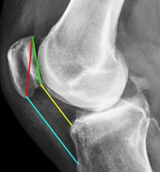

ACL Trauma

ACL Trauma Perception

“Expert” level perception of ACL trauma on knee xray exams (Segond fracture) using sparse data.